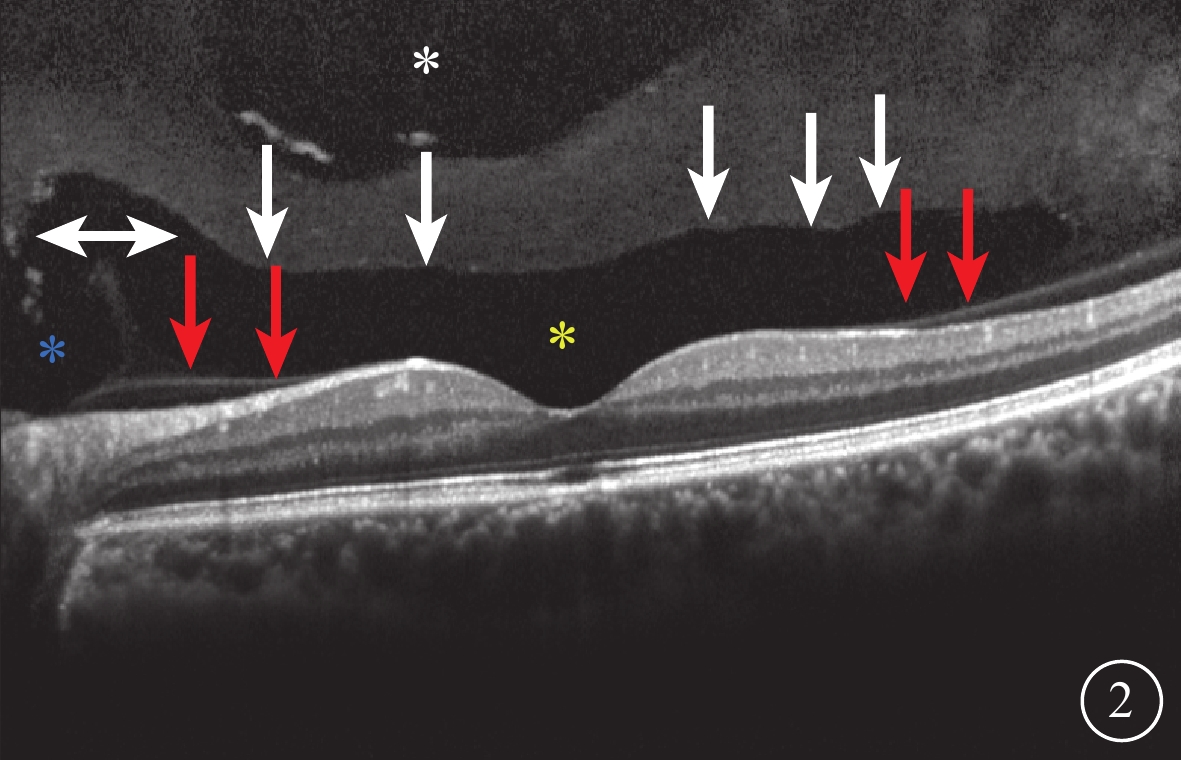

SD-OCT檢查,所有受檢眼常規檢查均未觀察到PPVP。后極部玻璃體掃描模式所采集的圖像可見PPVP結構清晰,表現為黃斑區前弱反射船形腔隙,前界為玻璃體膠原,后界為玻璃體皮質(圖2)。所有受檢眼PPVP鼻側存在一弱反射的無凝膠區域(Martegiani區),兩者之間有一隔膜將其分開。其中,單線掃描可見PPVP與Martegiani區之間存在連接通道(圖2)68只眼(66.0%);多線掃描可見所有受檢眼PPVP與Martegiani區存在連接通道,通道在某些層面出現(圖3)。PPVP前可見一個或多個黃斑上囊(圖2)16只眼(15.5%),其中黃斑上囊與PPVP之間相互連通(圖4)5只眼。PPVP伴玻璃體后脫離(PVD)(圖5)9只眼。采用FDI掃描模式進行檢查的21只眼,視網膜、脈絡膜成像清晰度較好,但玻璃體成像清晰度較差(圖4)。60只眼的PPVP平均最大水平距離為(6 895.7± 872.8)μm,平均垂直距離為(524.1±173.9)μm。

圖2

受檢眼SD-OCT像。黃斑區前船形弱反射區(黃色星),前界為玻璃體凝膠(白箭),后界為玻璃體皮質(紅箭);PPVP鼻側強反射隔膜樣結構將PPVP與Martegiani區(藍色星)隔開,之間有一短通道將兩者連通(白色雙箭);PPVP上方為另一弱反射區域即黃斑上囊(白色星)

圖2

受檢眼SD-OCT像。黃斑區前船形弱反射區(黃色星),前界為玻璃體凝膠(白箭),后界為玻璃體皮質(紅箭);PPVP鼻側強反射隔膜樣結構將PPVP與Martegiani區(藍色星)隔開,之間有一短通道將兩者連通(白色雙箭);PPVP上方為另一弱反射區域即黃斑上囊(白色星)

SD-OCT檢查,所有受檢眼常規檢查均未觀察到PPVP。后極部玻璃體掃描模式所采集的圖像可見PPVP結構清晰,表現為黃斑區前弱反射船形腔隙,前界為玻璃體膠原,后界為玻璃體皮質(圖2)。所有受檢眼PPVP鼻側存在一弱反射的無凝膠區域(Martegiani區),兩者之間有一隔膜將其分開。其中,單線掃描可見PPVP與Martegiani區之間存在連接通道(圖2)68只眼(66.0%);多線掃描可見所有受檢眼PPVP與Martegiani區存在連接通道,通道在某些層面出現(圖3)。PPVP前可見一個或多個黃斑上囊(圖2)16只眼(15.5%),其中黃斑上囊與PPVP之間相互連通(圖4)5只眼。PPVP伴玻璃體后脫離(PVD)(圖5)9只眼。采用FDI掃描模式進行檢查的21只眼,視網膜、脈絡膜成像清晰度較好,但玻璃體成像清晰度較差(圖4)。60只眼的PPVP平均最大水平距離為(6 895.7± 872.8)μm,平均垂直距離為(524.1±173.9)μm。

圖2

受檢眼SD-OCT像。黃斑區前船形弱反射區(黃色星),前界為玻璃體凝膠(白箭),后界為玻璃體皮質(紅箭);PPVP鼻側強反射隔膜樣結構將PPVP與Martegiani區(藍色星)隔開,之間有一短通道將兩者連通(白色雙箭);PPVP上方為另一弱反射區域即黃斑上囊(白色星)

圖2

受檢眼SD-OCT像。黃斑區前船形弱反射區(黃色星),前界為玻璃體凝膠(白箭),后界為玻璃體皮質(紅箭);PPVP鼻側強反射隔膜樣結構將PPVP與Martegiani區(藍色星)隔開,之間有一短通道將兩者連通(白色雙箭);PPVP上方為另一弱反射區域即黃斑上囊(白色星)